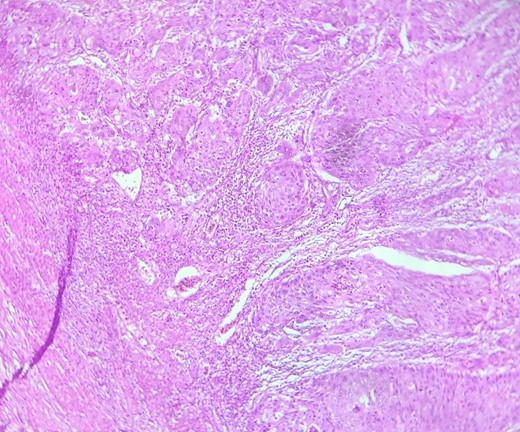

HE section: Neoplastic cells have densely chromatic enlarged nuclei with prominent nucleoli. They are enlarged with abundant eosinophilic cytoplasm and focal keratinization. Intercellular bridges are slightly visible (x200).